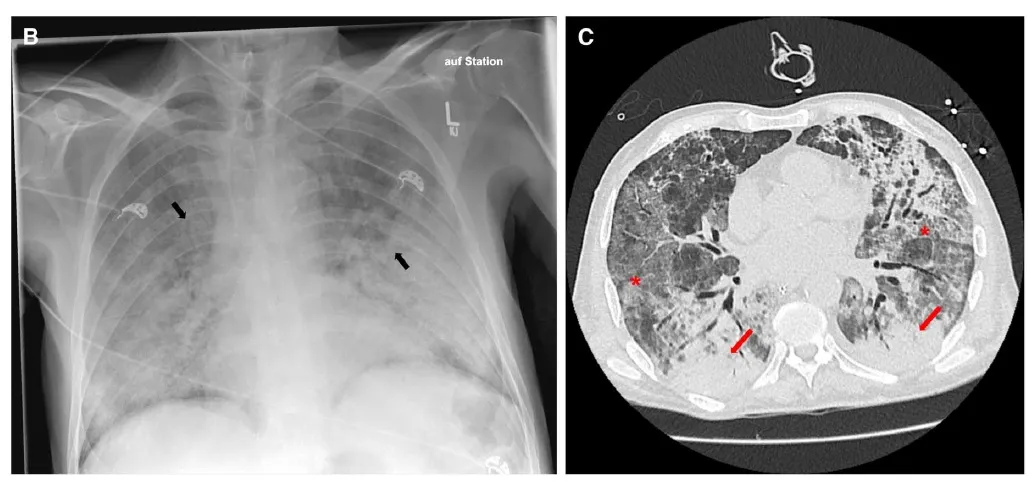

Uma causa incomum de hematúria glomerular intermitente!

Hematúria pós infecção, caso clínicos para auxiliar no entendimento de causas glomerulares comuns e raras...